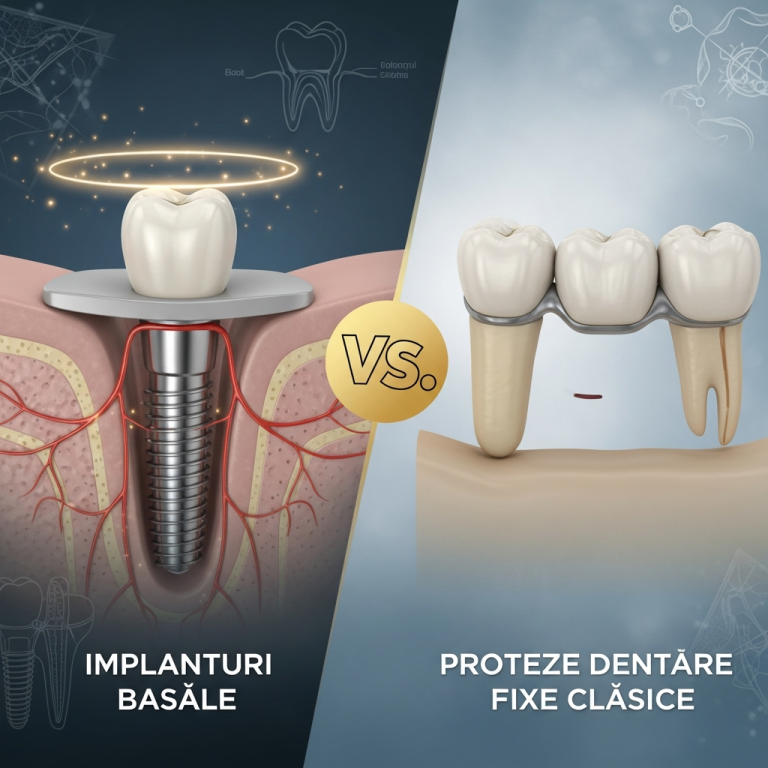

Implanturile bazale, cunoscute și sub denumirea de bicorticale monobloc, sunt sisteme de fixare dentară special concepute pentru ancorarea în ambele corticale osoase (vestibulară și linguală/palatală). Spre deosebire de implanturile clasice, care se sprijină predominant pe osul spongios, acestea utilizează structura corticală densă pentru o stabilitate imediată excepțională. Designul monobloc integrează corpul implantului și pilarul într-o singură piesă, ceea ce elimină riscul de micro-deplasare la interfață și permite adesea o încărcare imediată.

Diferențe și indicații (bicorticale principal, clasice referință)